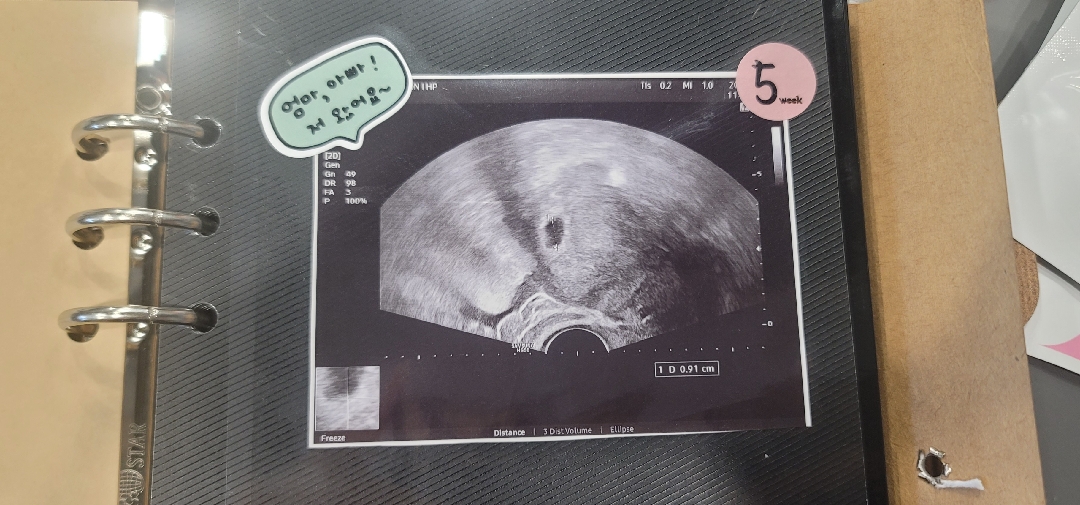

아기집보고왓는데 난황을못봣어여ㅠㅠ

5주1일차에 아기집은봣는데ㅠㅠ난황을못봣어요ㅠㅠ16일에난황보러가는데걱정이네요ㅠㅠ

초음파사진에희미하게보이는거같은데ㅠㅠ원장님이아무말씀없으셧어서ㅠㅠ걱정되네요ㅠ